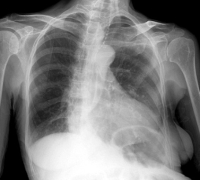

A szív megnagyobbodása sokszor mellkasröntgen-felvételen tűnik fel, de az azt kiváltó pontos elváltozás diagnózisának felállításához más vizsgálatokra, a szív funkcióit kimutatni képes EKG- (elektrokardiográfia) vagy echokardiográfia-vizsgálatra is szükség van, illetve sor kerülhet CT-re, MRI-re, angiográfiára, biopsziára és vérvizsgálatokra is.